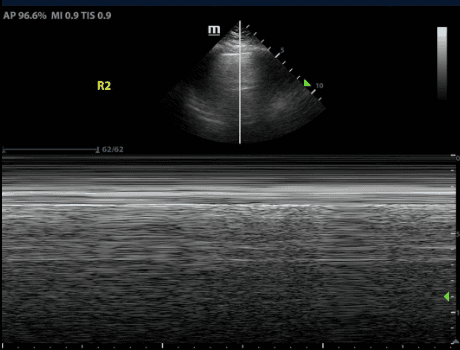

M-mode, or Motion mode, is a type of ultrasound modality that displays motion of a structure through time. In order to detect lung sliding with M-mode, place the M-mode cursor through the pleural line. In the presence of lung sliding, the machine will display an image that is often referred to as the “sea-shore sign” or “waves on a sandy beach.” This stratified appearance is due to the difference in movement between the chest wall versus the pleural line and lung. The motionless chest wall appears as waves while the mobile pleura and lung reflect a sandy beach.

If lung sliding is absent, M-mode will reflect an image of uniform horizontal straight lines known as the “stratosphere sign” or the “barcode sign.” This is because the immobile pleura looks similar to the chest wall.